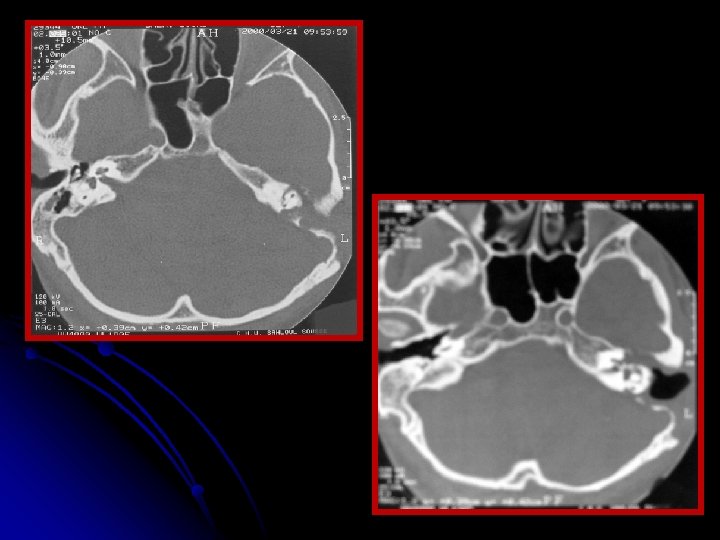

ØLe scanner des rochers montrait un cholestéatome qui contourne le labyrinthe et s'étend jusqu‘au CAI et au golfe de la jugulaire. ØLa patiente a eu dans un 2ème temps opératoire, une voie transcochléaire avec comblement de la cavité par de la graisse abdominale a été réalisée. ØLes suites opératoires étaient simples. ØRecul sans récidive : 4 ans.

Extension sus labyrinthique Extension sous labyrinthique

Imagerie : diagnostic positif+++ • La TDM en coupes millimétrées en incidences axiale et coronale permet une appréciation précise de la destruction osseuse. • Cette destruction peut être due à une érosion de l’os par effet de pression entraînant une ischémie, à une hyperactivité ostéoclastique.

• La TDM objective une lacune polycyclique à contours arrondis, de nature avasculaire. • Elle précise l'extension et apprécie les refoulements dure-mériens. • Elle permet également de faire le diagnostic différentiel avec d’autres processus pathologiques intrapétreux